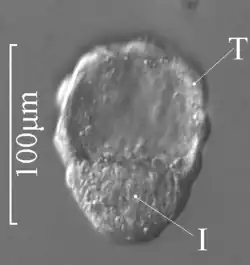

Blastocysta

I – węzeł zarodkowy

T – trofoblast

Blastocysta – blastula łożyskowców, stadium rozwoju zarodkowego. Składa się z trofoblastu i węzła zarodkowego (embrioblast)[1]. Następuje po stadium rozwoju moruli. W stadium blastocysty zarodek zagnieżdża się w śluzówce macicy. Z komórek węzła zarodkowego niektórych ssaków (człowieka, myszy) uzyskano hodowle zarodkowych komórek macierzystych, mających zdolność samoodnawiania się i wytwarzania wszystkich rodzajów komórek.